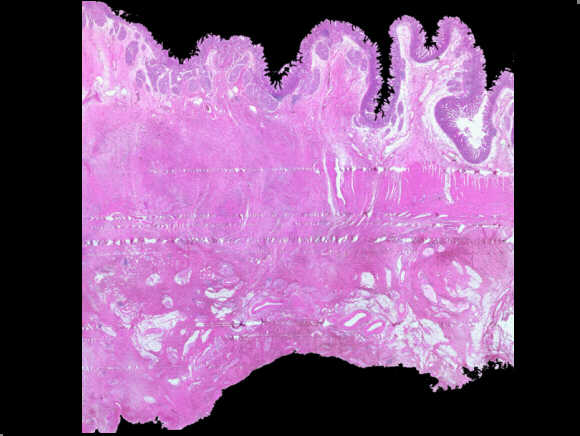

Duodenal wall in a “groove pancreatitis”. The histological important sign is the hypertrophy and the fibrosis of the muscolaris propria and the expansion of the “groove,” a virtual space, in the posterior face of the pancreata, between duodenum, pancreata and choledocus.

Low-power view of a autoimmune pancreatitis showing a periductular inflammatory cells. The remainder of pancreatic tissue is fibrotic with complete acinar atrophy.

High-power view of the same slide shows the heavy inflammatory infiltrate in the epithelium layer with erosion and duct distorsion.